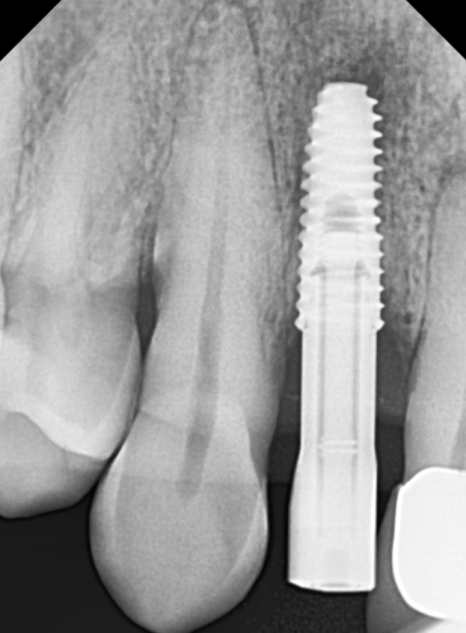

내원 당시 오른쪽 앞니(#12)가

심하게 흔들리고 있었고,

바로 옆 중앙 앞니(#11)도

잇몸뼈가 많이 내려가 영향을 받고 있었습니다.

240612

CT 분석 결과 중앙 앞니(#11) 치아 뿌리 끝에

염증이 발견되었지만,

환자분께서 최대한 자기 치아를

더 써보고 싶어 하셔서

일단 흔들림이 심한 오른쪽 앞니(#12)만

발치하고 임플란트를 진행했습니다.